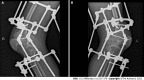

Case summary: This report presents a case study of a 31-year-old male patient with a squatting gait due to severe bilateral KFC and HFC. The patient had a normal walking pattern until the age of eight, after which he experienced knee and hip pain, leading to the gradual development of KFC and HFC. The patient's primary complaint was an inability to walk upright. The patient was diagnosed with JoAS and underwent hip dissection and release, limited soft tissue release of the hamstring, and gradual traction using the Ilizarov method. Ultimately, the patient was able to walk upright.

Conclusion: The incidence of squatting gait due to KFC in individuals diagnosed with JoAS was low. Utilizing the Ilizarov technique has proven to be a secure and effective method for managing KFC in JoAS patients. Although the Ilizarov technique cannot substitute for total knee arthroplasty (TKA), its application can delay the need for primary TKA in JoAS patients and alleviate the intricacy and potential complications associated with the procedure.